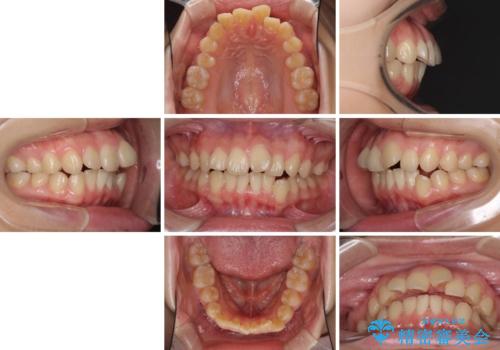

デコボコで飛び出した前歯をきれいに インビザラインによる矯正治療

- デコボコと飛び出した前歯を治したいとのことで来院された患者様です。

ゴムかけを活用して上顎歯列全体を後方移動し、IPR(歯と歯の間を削る)によってデコボコが解消するように設計し、インビザラインにより治療を行うこととしました。

後方移動に際し、上下顎の親知らずは4本とも抜歯することとしました。

毎日しっかりと装着してくださったので、概ねシミュレーション通りに歯を移動させることができました。

治療前には接触することのなかった上下の前歯が接触するようになり、食事の際前歯でものをかみ切れるようになりました。

気にしていた口元の印象が改善され、患者様には大変満足していただきました。